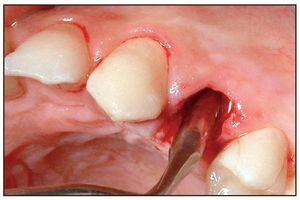

La extracción se efectuó usando las puntas del equipo de extracción (figura 1). La punta en forma de flecha se introdujo en el surco a una profundidad de 4-5 mm sin separar primero la encía del diente, alrededor de toda la circunferencia de éste. No se evidenció hemorragia mientras se progresaba en dirección apical (figuras 3a y 3b). Acto seguido, se usaron sindesmotomos rectos o angulados para cortar en profundidad las fibras del LPD (hasta 10 mm o más). Tras la sección de las fibras del ligamento, el diente se movilizó con un sindesmotomo de Claude Bernard (figura 3c) y se extrajo del alveolo con unas pinzas (figura 3d). En el caso de dientes anquilosados, se usaron sindesmotomos de vibración para desprender la raíz del hueso fijado circundante.

Figura 3 Procedimiento de extracción con las puntas vibratorias.

Figuras 3a y 3b La punta en forma de flecha se introdujo en el ligamento periodontal en el lado distal (derecha) y el lado mesial (izquierda) del diente afectado.